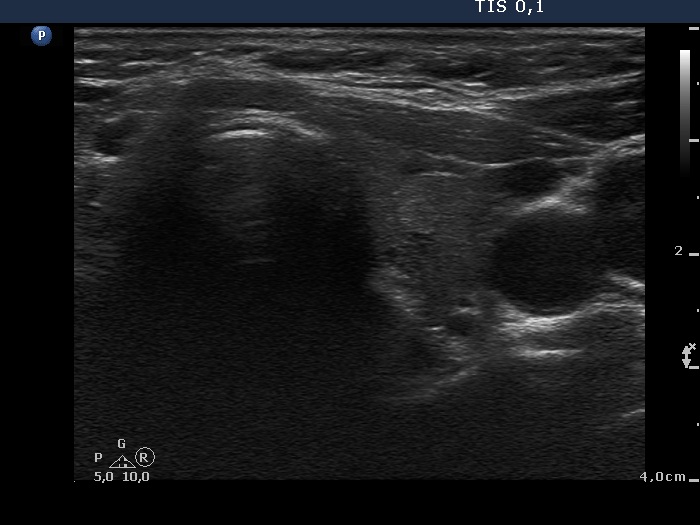

Parathyroid lesions - case 39 (ultrasonographic picture 5)

Left lobe, transverse scan. This lobe presents small insignificant lesions.